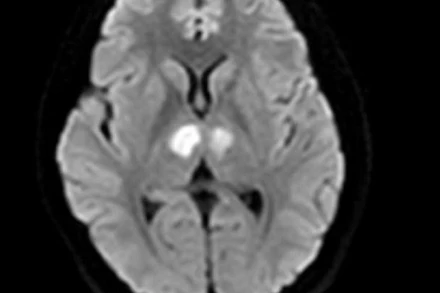

Vì tin vào thuốc giảm cân, một nữ bệnh nhân đã bị teo hẹp toàn bộ dạ dày và thực quản do hóa chất, phải cắt toàn bộ dạ dày và thực quản ngực.